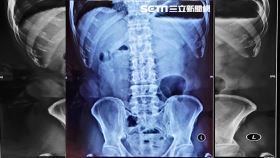

她吃魚…結果魚刺一路過關斬將險要命

一位八十歲的老太太因為發燒又腹痛,被家人緊急送到急診...

2018/07/12 08:19